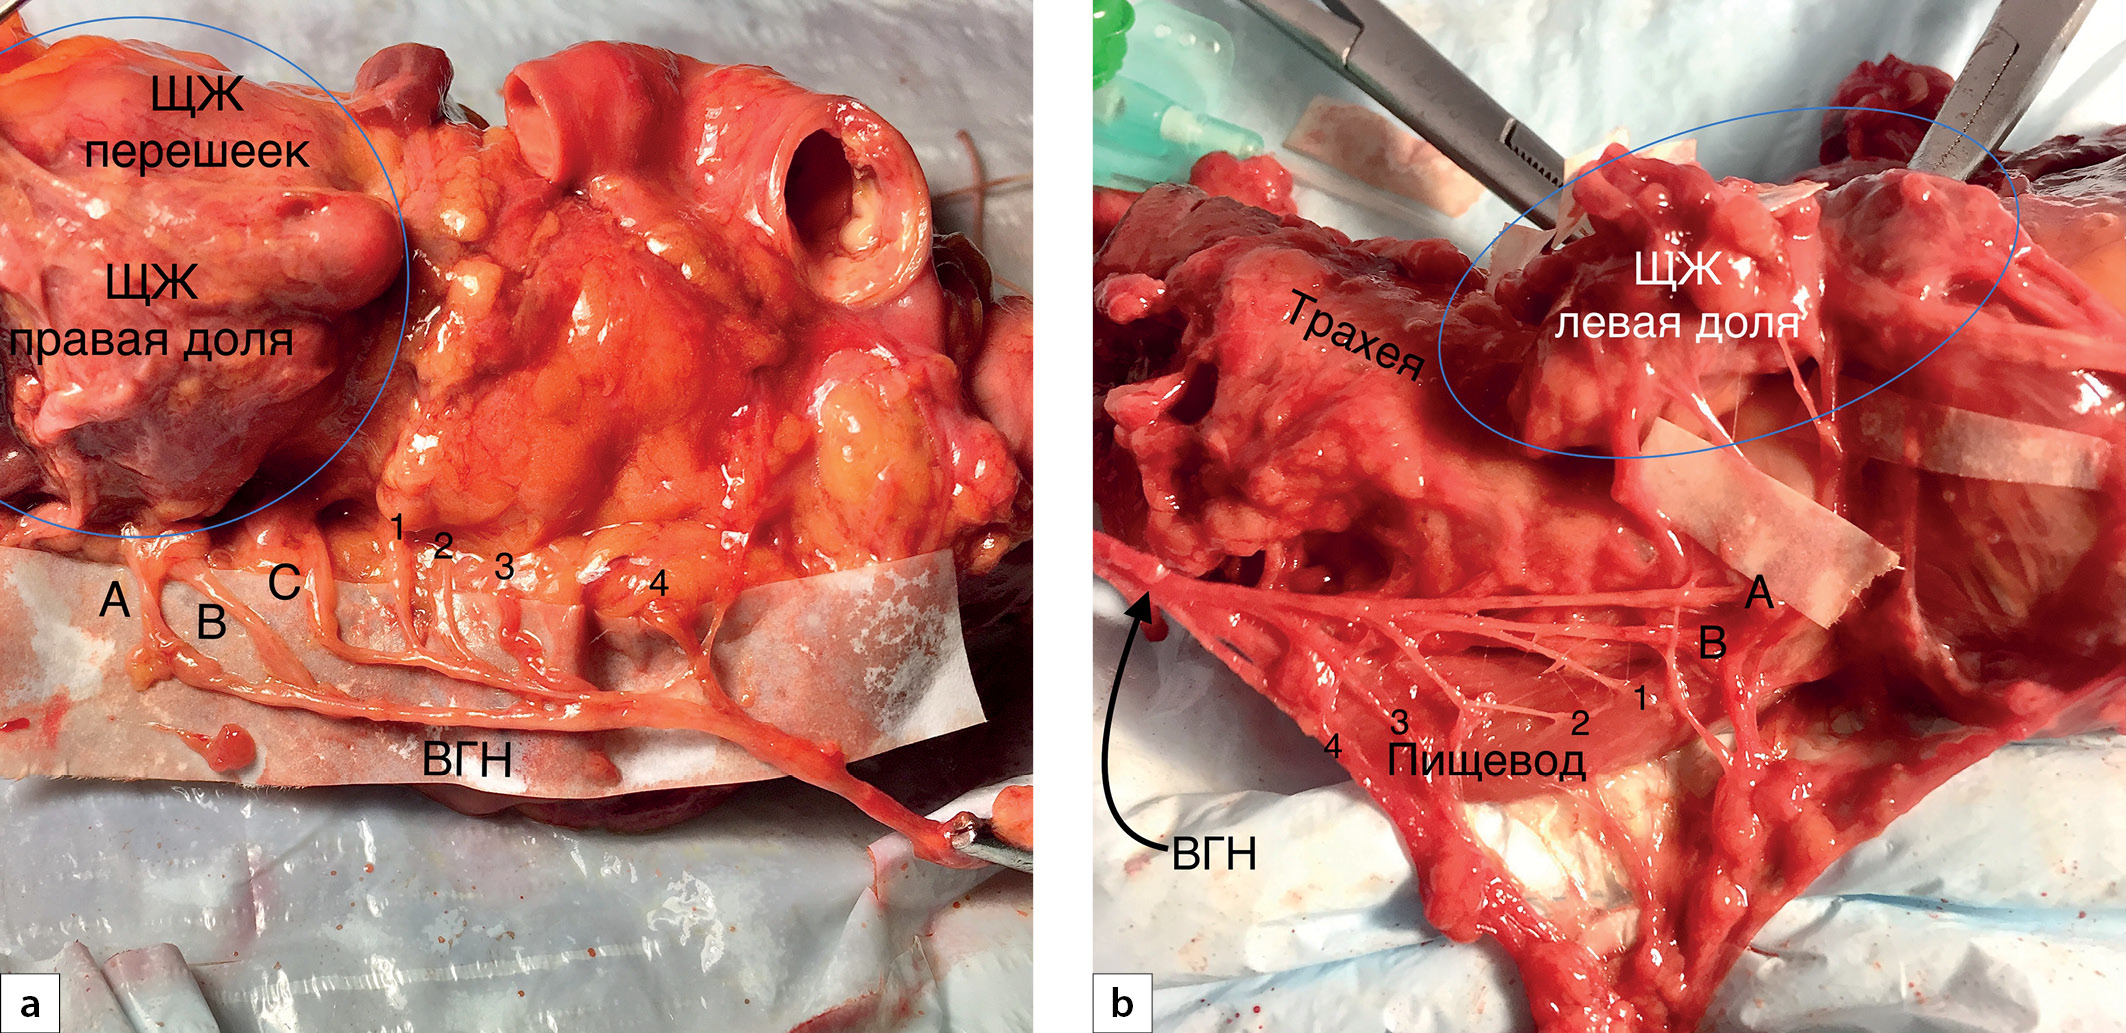

Трахеопищеводные ветви возвратного гортанного нерва

Все ВГН (46 наблюдений) находились в трахеопищеводной борозде и имели типичное восходящее направление. При тракции основного ствола нерва латеральнее в этой области визуализировались тонкие ветки, направляющиеся от ВГН к трахее и пищеводу (рис. 1). Количество трахеопищеводных веток варьировало от 4 до 10 (6±2), а их длина — в диапазоне от 4 до 35 мм (11±4 мм). Различий в длине ветвей справа и слева не отмечено (р=0,185). Однако количество трахеопищеводных ветвей статистически значимо определялось больше с левой стороны (р=0,032).

Кроме того, в 3 (6,5%) случаях левые трахеопищеводные ветви имели значительную протяженность, направлялись параллельно основному стволу ВГН вплоть до перстнещитовидного сочленения, отдавая по ходу своему ветки к трахее и пищеводу (рис. 2).

Рис. 1. Трахеопищеводные и гортанные ветви возвратного гортанного нерва (ВГН).

1, 2, 3, 4 — трахеопищеводные ветви. A, B, C — гортанные ветви.

Рис. 2. Длинные трахеопищеводные ветви возвратного гортанного нерва (отмечены тонкими прямыми стрелками). А, В — гортанные ветви.

Гортанные ветви возвратного гортанного нерва

Все 46 (100%) ВГН «проникали» в гортань в области перстнещитовидного сочленения (в проекции бугорка Цукеркандля), продолжая далее свой ход под пластинкой щитовидного хряща (интраларингеально). В половине (47,8%) случаев отмечена экстраларингеальная бифуркация нерва. В 12 (26,1%) наблюдениях до «входа» в гортань ВГН образовывал три ветви и только в 3 (6,5%) случаях — четыре ветви (табл. 1, рис. 3).

Рис. 3. Гортанные ветви возвратного гортанного нерва (ВГН).

a — две гортанных ветви; b — три гортанных ветви; c — четыре гортанных ветви. А, B, C, D — гортанные ветви. НОЩЖ — нижняя околощитовидная железа.